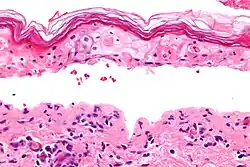

| Lesões características da síndrome de Stevens–Johnson | |

| Método de diagnóstico | <10% da pele envolvida, biópsia da pele[2] |

Para o diagnóstico de SSJ é necessário que a área de pele afetada seja inferior a 10% da superfície do corpo.[2] Quando mais de 30% da pele é afetada considera-se NET, e entre 10 e 30% considera-se forma intermédia.[3] Acredita-se que as reações SJS/TEN seguem um mecanismo de hipersensibilidade do tipo IV (não imediata).[5] A SSJ/NET faz parte de um grupo de doenças denominado reações adversas cutâneas graves (SCAR), do qual também fazem parte a síndrome induzida por fármacos com eosinofilia e sintomas sistémicos (síndrome DRESS) e a pustulose exantemática generalizada aguda (PEGA).[6] O eritema multiforme (EM) é geralmente considerado uma doença distinta.[7]